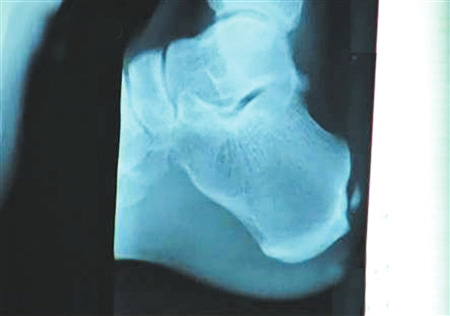

組圖:劉翔跟腱手術全過程揭秘

手術要取出的鈣化物就在這里。 圖片來源:華西都市報

北京時間12月6日凌晨,備受關注的中國飛人劉翔在休斯頓赫曼紀念醫(yī)院的跟腱手術成功結束。